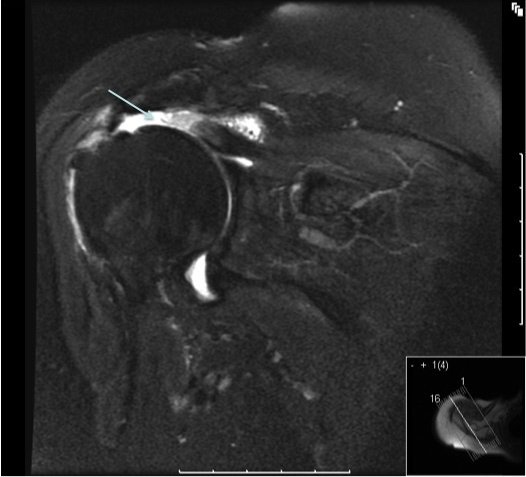

Rotator Cuff Tear Mri

The condition usually commences with a gradual onset of pain in the shoulder. A diagnosis of Rotator cuff tear is made based on the history of a painful shoulder and/or weakness. Pain is usually intermittent and experienced when reaching overhead or when lying on the shoulder at night. The arm may tire more easily with activity. Individuals may find it difficult to raise the arm above the shoulder. A tear should be suspected if weakness develops in the shoulder after an injury. Examination shows pain with certain movements of the shoulder and weakness on special rotator cuff tests. An X-ray is essential to look at the shape of the acromion and the rest of the joint. An ultrasound scan may confirm the diagnosis. Special imaging with an MRI scans is sometimes necessary to obtain further information about the location and size of the rotator cuff tear, the state of the joint and the muscles of the rotator cuff.